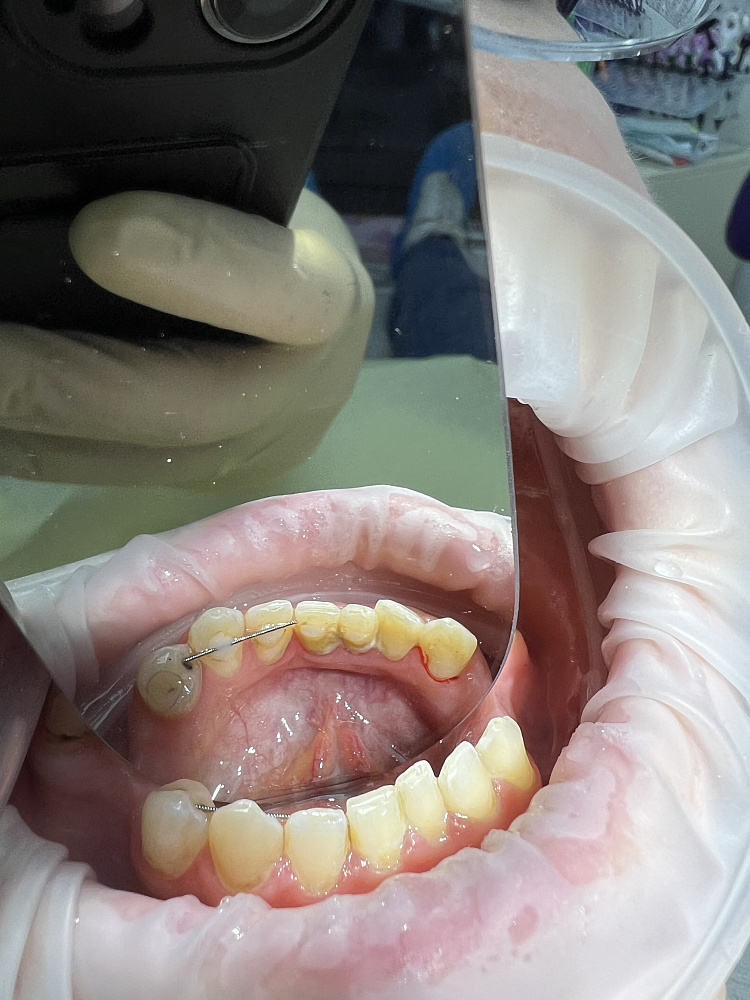

Профессиональная гигиена полости рта — это комплексная профилактическая процедура, направленная на удаление зубных отложений и поддержание здоровья дёсен. Во время процедуры врач последовательно очищает поверхность зубов от твёрдых и мягких отложений, снижая риск кариеса, воспаления дёсен и неприятного запаха изо рта. Профессиональная гигиена проводится с использованием современных методик и подходит пациентам любого возраста как самостоятельная профилактика, так и подготовка к лечению.

Регулярная профессиональная гигиена полости рта позволяет поддерживать чистоту зубов в тех зонах, которые недоступны для домашнего ухода. После удаления камня и налёта поверхность зубов становится более гладкой, что замедляет повторное образование отложений. Завершающее фторирование снижает чувствительность эмали и повышает её устойчивость к кариесу. Процедура рекомендована как профилактическая мера, а также перед отбеливанием, ортопедическим и терапевтическим лечением. Проведение профессиональной гигиены помогает сохранить здоровье зубов и дёсен, улучшить внешний вид улыбки и продлить результат последующего стоматологического лечения.